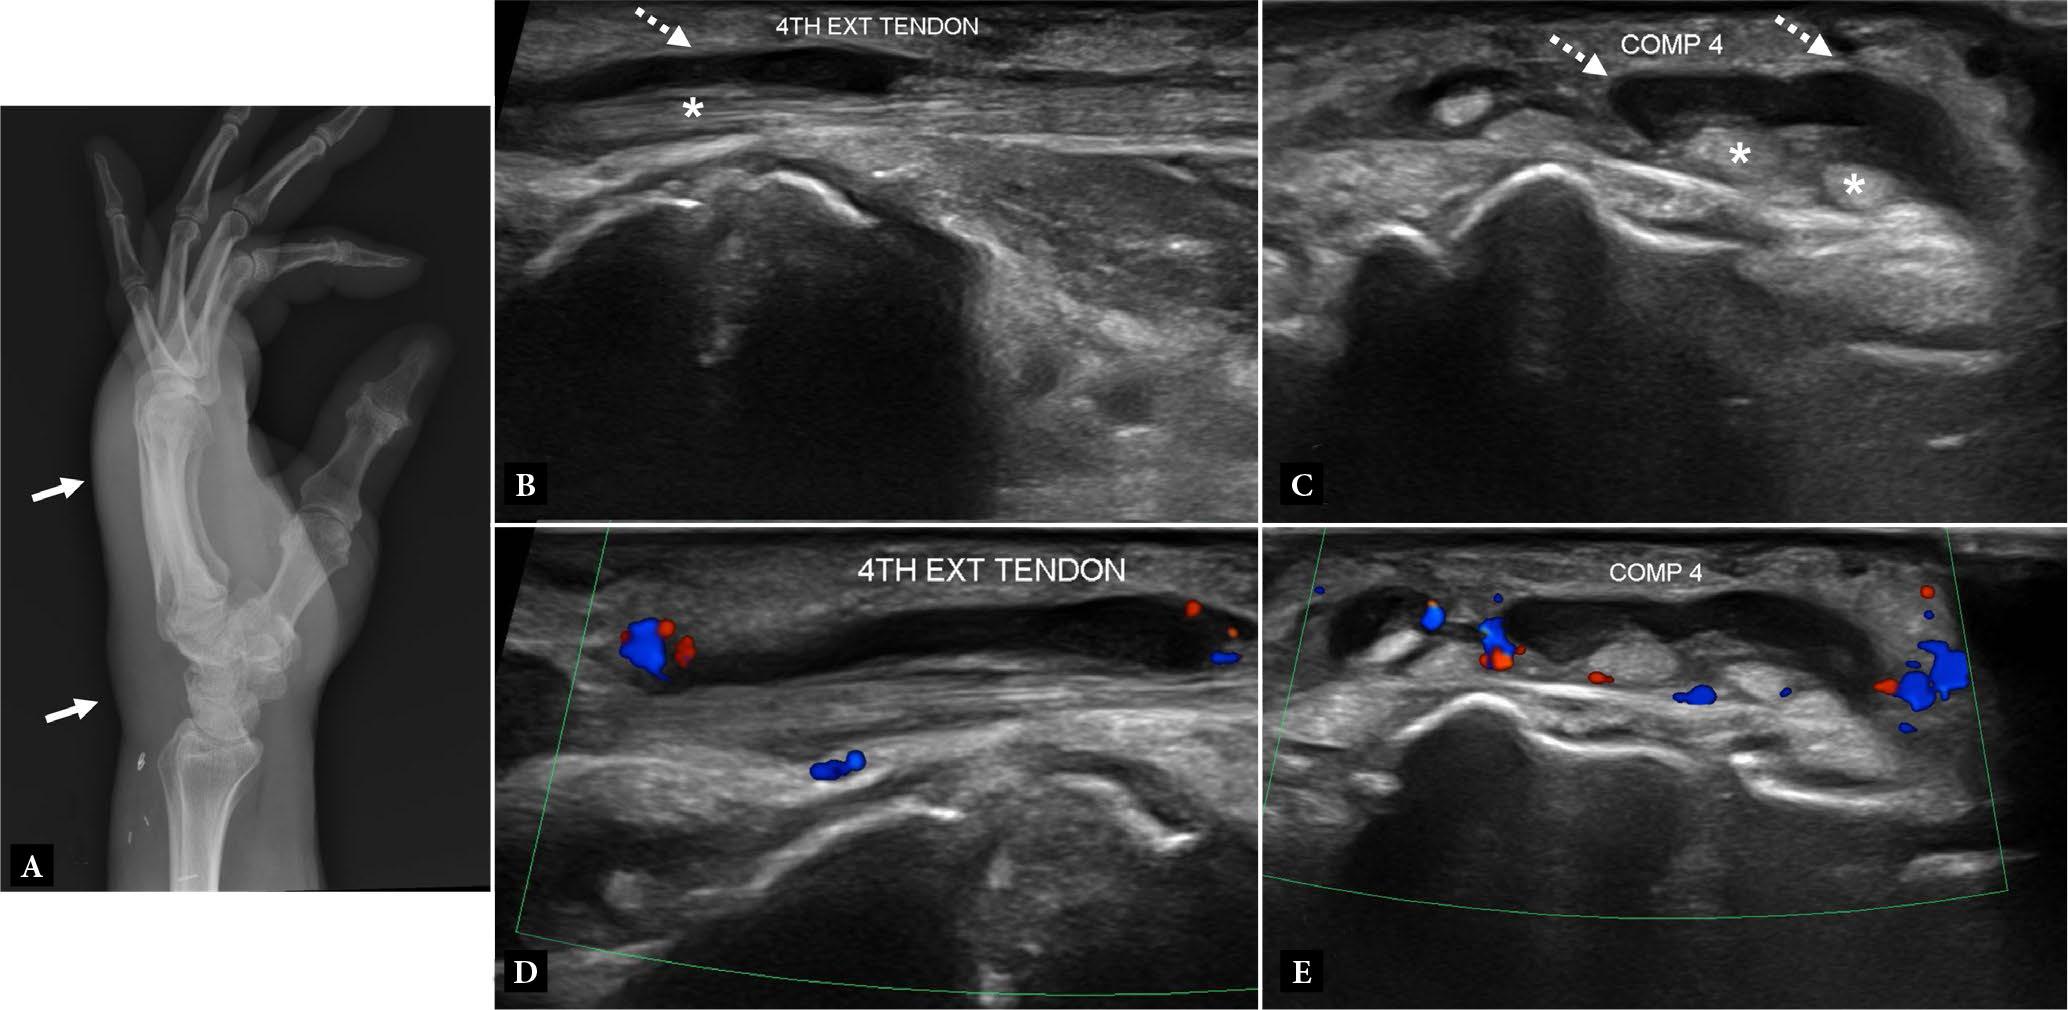

Fig. 1.